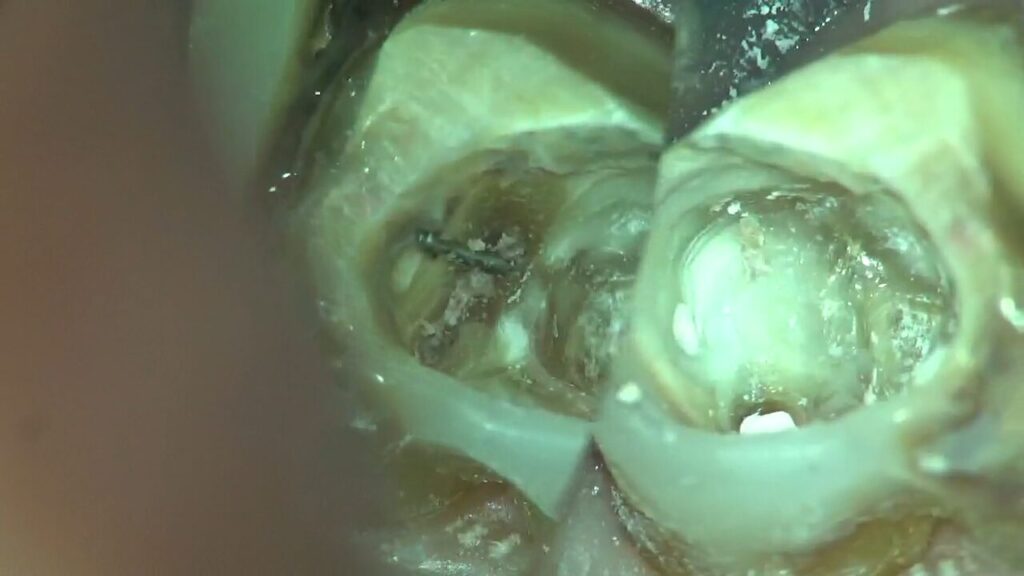

【治療例】エビデンスを重視した米国式精密根管治療

高田歯科クリニックでは、東京科学大学(旧:東京医科歯科大学)が発表した「顕微鏡を用いた歯内治療(Microendodontics)」をはじめ、高い有効性を数多く報告されている米国式精密根管治療を採用。

米国の根管治療専門医が標準的に使用する、マイクロスコープ・歯科用CT・ラバーダムに加え、歯の根(根管)の複雑な形状に対応し、柔軟な治療を可能とするニッケルチタンファイルを取り入れています。

マイクロスコープを用いて一度の処置に時間をかけて丁寧に治療することで、患部の取り残しや唾液の侵入による再感染のリスクを低減し、成功率の向上を目指すとともに、トータルの通院回数・期間の短縮にも貢献します。

虫歯治療・根管治療・歯周病治療・補綴治療(審美治療)のすべてにマイクロスコープを使用し、精密に処置を行うことで、多くの歯を残せることが多くなっています。

マイクロスコープを使った精密な歯科治療だからこそできる処置として、パーフォレーションリペア(穿孔封鎖)があります。

パーフォレーションとは、根管治療などの治療過程で偶発的に開いてしまった穴のことで、歯科医師による誤った処置や、虫歯などで歯質が弱くなっているときに発生しがちです。

放置すると歯周病や顎の骨への細菌感染につながり、最悪の場合に抜歯に至るため、速やかな処置が重要です。

パーフォレーションリペアでは、マイクロスコープを使った拡大視野下で治療を行い、MTAセメントと呼ばれる生体親和性(体へのなじみ)が高い素材を使って穿孔部を封鎖します。

このように、他の歯科医院で「抜歯するしかない」と言われたような難しいケースでも、マイクロスコープを使った精密歯科治療では、ご自身の歯を残せる可能性があります。

セカンドオピニオンで痛みの原因を特定|破折したリーマーやファイルの除去

たとえば、他の歯科医院で受けた根管治療の際、リーマー(細い器具)が破折して歯根(歯の根っこ部分)の中に取り残されていたケースがありました。

肉眼に頼った治療では見落としてしまいがちな痛みの原因についても、マイクロスコープを用いて丁寧に除去していき、「何度も繰り返さない治療」を目指しています。